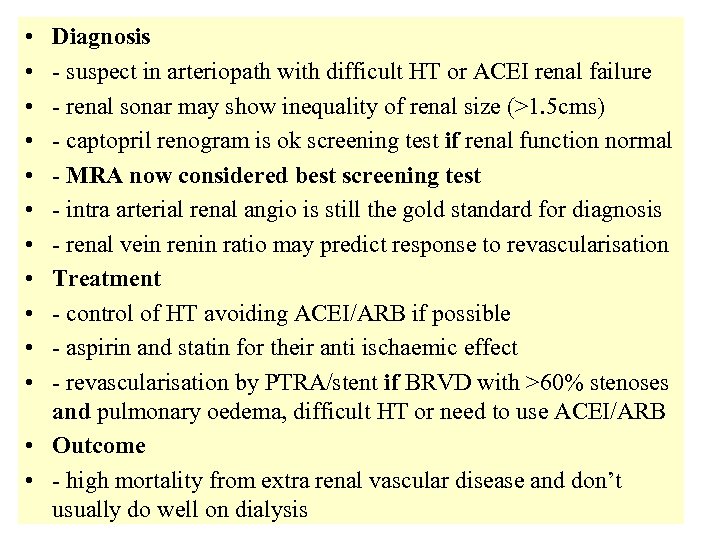

• • • Diagnosis - suspect in arteriopath with difficult HT or ACEI renal failure - renal sonar may show inequality of renal size (>1. 5 cms) - captopril renogram is ok screening test if renal function normal - MRA now considered best screening test - intra arterial renal angio is still the gold standard for diagnosis - renal vein renin ratio may predict response to revascularisation Treatment - control of HT avoiding ACEI/ARB if possible - aspirin and statin for their anti ischaemic effect - revascularisation by PTRA/stent if BRVD with >60% stenoses and pulmonary oedema, difficult HT or need to use ACEI/ARB • Outcome • - high mortality from extra renal vascular disease and don’t usually do well on dialysis

• • • Diagnosis - suspect in arteriopath with difficult HT or ACEI renal failure - renal sonar may show inequality of renal size (>1. 5 cms) - captopril renogram is ok screening test if renal function normal - MRA now considered best screening test - intra arterial renal angio is still the gold standard for diagnosis - renal vein renin ratio may predict response to revascularisation Treatment - control of HT avoiding ACEI/ARB if possible - aspirin and statin for their anti ischaemic effect - revascularisation by PTRA/stent if BRVD with >60% stenoses and pulmonary oedema, difficult HT or need to use ACEI/ARB • Outcome • - high mortality from extra renal vascular disease and don’t usually do well on dialysis